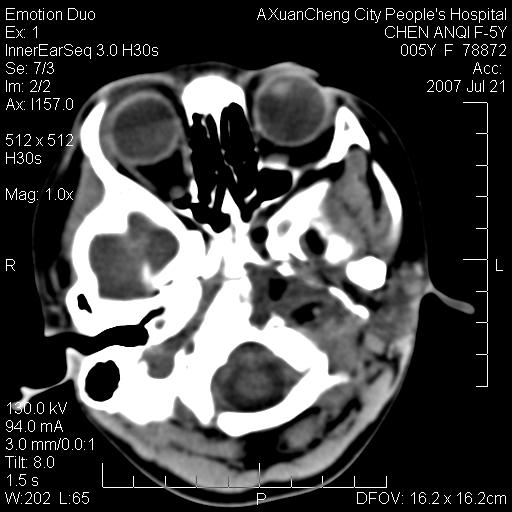

标题: PED0273:5岁,左耳流脓痛疼一周,颅底骨质破坏 [打印本页]

标题: PED0273:5岁,左耳流脓痛疼一周,颅底骨质破坏

患儿5岁,左耳流脓痛疼一周,左外耳道肉芽组织填塞 软组织窗显示病灶内结节状低密度影为气体密度

1.左耳中耳炎. 2.考虑伴颅内感染.

颅底骨质破坏,建议增强扫描

左侧中耳炎并胆脂瘤,左颞骨岩部骨质破坏并颅内感染积气。

考虑化脓性中耳乳突炎伴胆脂肪瘤形成并左颞叶感染,不除外合并嗜酸性肉芽肿.

补充:腺样体肥大.